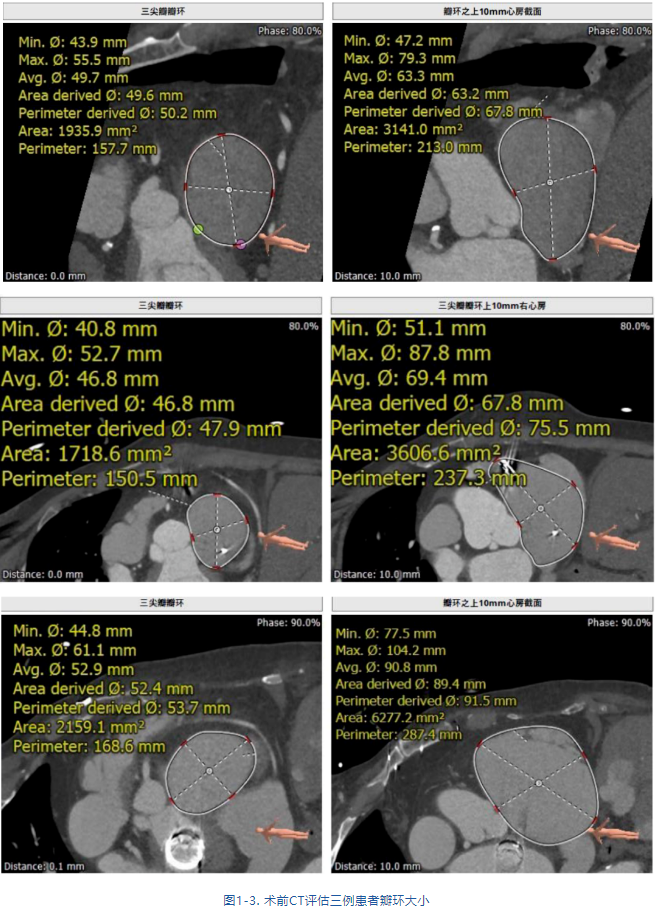

接受治療的是三例重度三尖瓣反流患者,術(shù)前基礎(chǔ)疾病多,均患有嚴重心律失常,其中兩例患者NYHA心功能Ⅱ/Ⅲ級。結(jié)合術(shù)前CT評估結(jié)果,三例患者的自體瓣環(huán)都較大(圖1-3),最大者平均瓣環(huán)為53.7mm;有一例患者有起搏器植入史,術(shù)中操作有纏繞起搏器導(dǎo)線的風(fēng)險;三例患者入路血管均無嚴重迂曲和鈣化。經(jīng)術(shù)前討論分析,潘湘斌教授及其團隊潘家華教授、朱達教授、王首正教授以及心超室的駱志玲教授,董念國教授及其團隊謝明星教授、尚小珂教授、陳澍教授、鐘禹成教授經(jīng)過討論決定,采用創(chuàng)新的 LuX-Valve Plus經(jīng)血管三尖瓣置換系統(tǒng)對患者進行手術(shù)。LuX-Valve Plus是我國自主研發(fā)的經(jīng)血管介入三尖瓣置換系統(tǒng),經(jīng)頸靜脈入路的微創(chuàng)方式可進一步降低對患者的創(chuàng)傷。